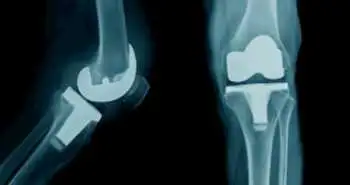

Внутрішньосуглобове введення спріферміна (рекомбінантного фактора росту людських фібробластів 18) було визнано безпечним у пацієнтів з деформуючим остеоартрозом (ДOA) колінного суглоба, як показало дослідження, результати якого опубліковані в Arthritis Research & Therapy.